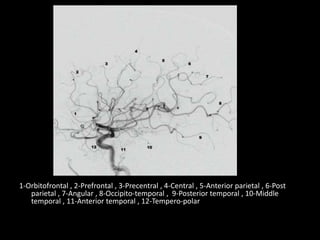

1-Orbitofrontal , 2-Prefrontal , 3-Precentral , 4-Central , 5-Anterior parietal , 6-Post

parietal , 7-Angular , 8-Occipito-temporal , 9-Posterior temporal , 10-Middle

temporal , 11-Anterior temporal , 12-Tempero-polar